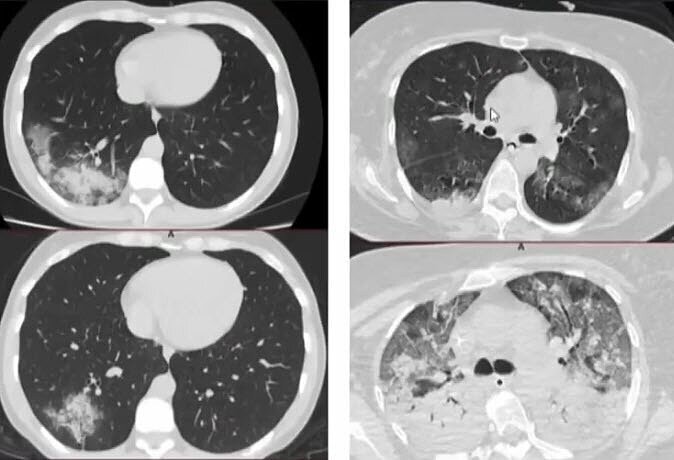

Кт динамика

Кт динамика 110 фото